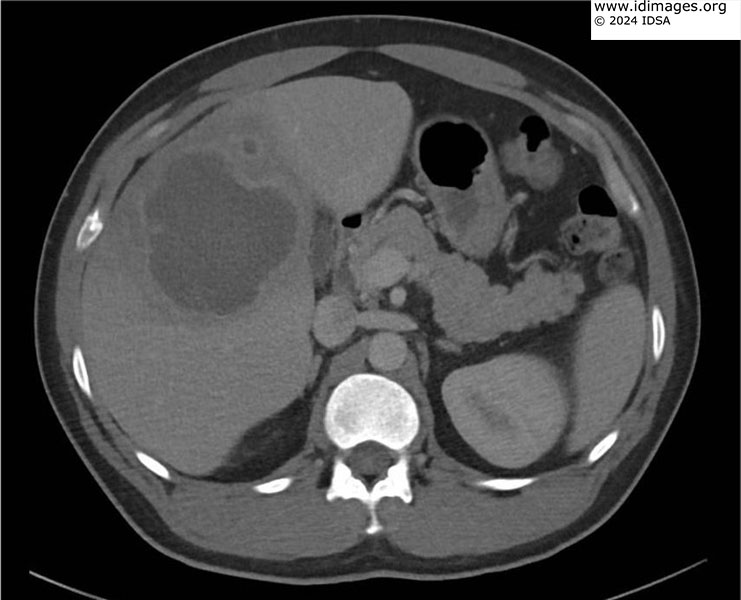

What is the diagnosis?